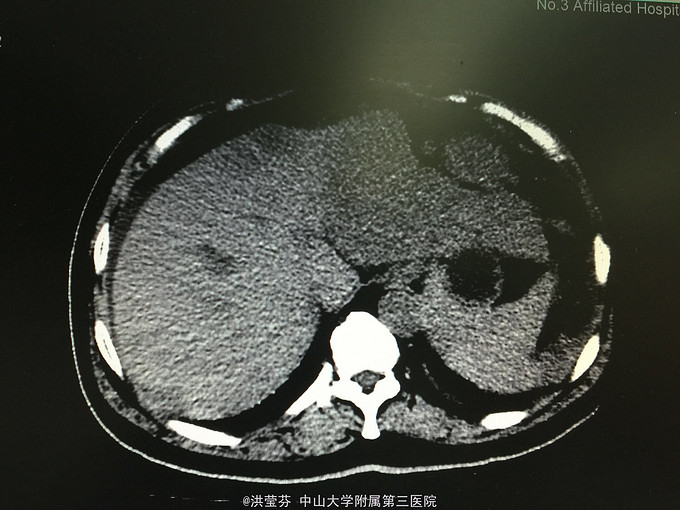

查体:上腹部轻压痛,无反跳痛。 辅助检查:上腹部CT增强提示:肝S2/3/4段恶性肿瘤,肝内多发子灶,肝左静脉及门静脉左、右支受侵;腹腔多发转移瘤;肝门部、腹膜后多发肿大淋巴结;门静脉海绵样变;少量腹水。胸部CT提示:1、双肺多发小结节,结合病史,考虑转移瘤;纵膈、双侧肺门多发肿大淋巴结。2.双肺炎症;左侧胸腔少量积液。CA125 555.1IU/nl,CA199 1093.5IU/nl。

诊断考虑胆管细胞癌可能性大,予完善肝穿刺,活检病理示:符合中分化腺癌,胆管细胞癌可能性大。免疫组化结果示:Hep(-),CK(+),CK19(+),CEA(-),CDX-2(-),DK20(-),Ki 67(约15%),TTF-1(-)。诊断明确肝内胆管细胞癌,IV期,无明显化疗禁忌,予GP方案化疗,辅以护胃、护肝、止吐等治疗。